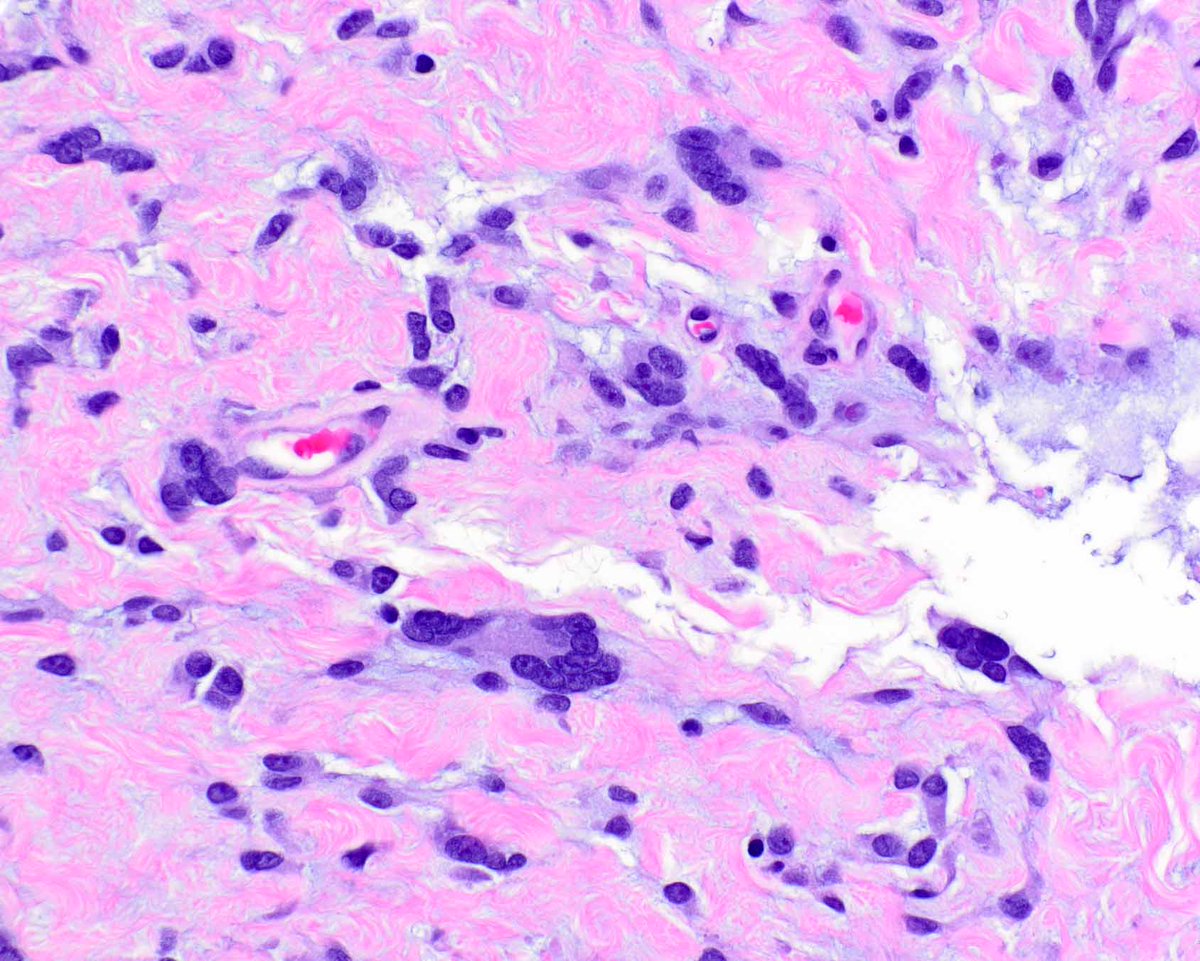

This is an example of a dermatofibrosarcoma protuberans (DFSP) arising in association with a giant cell fibroblastoma, the latter considered a forme fruste DFSP. #UMiamiPath @ModernPathology @science_press

LizMontgomeryMD's tweet image. This is an example of a dermatofibrosarcoma protuberans (DFSP) arising in association with a giant cell fibroblastoma, the latter considered a forme fruste DFSP. #UMiamiPath @ModernPathology @science_press